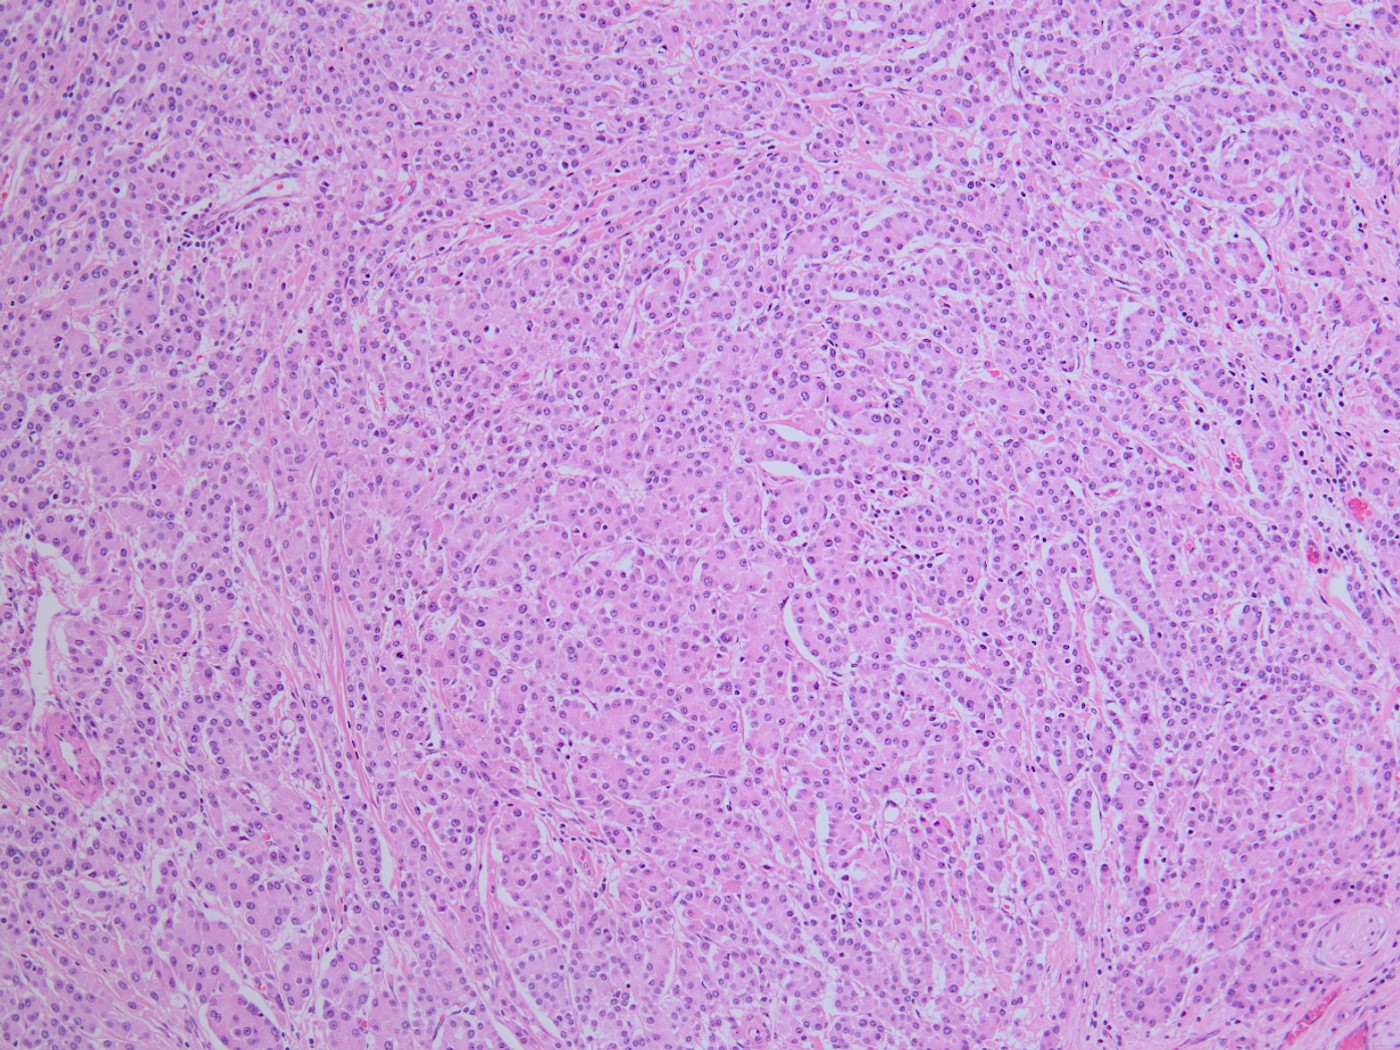

A 75-year-old woman with suspected pancreatic NET undergoes a Whipple. The morphology of the tumor is seen in Fig A-D. A synaptophysin is performed (Fig E). What additional IHC profile can be expected in this tumor?

The tumor is solid and cellular with the individual cells displaying abundant granular cytoplasm and round monotonous nuclei with prominent nucleoli, configured in a vague acinar formation. These features are consistent with an acinar cell carcinoma, therefore positive staining for trypsin and BCL10 are expected (figures).

The main differential diagnosis in this case is a well differentiated neuroendocrine tumor. However, a stain for synaptophysin stain is negative, with an islet serving as an internal control. This finding rules out a neuroendocrine tumor, therefore chromogranin would also likely be negative. Acinar cell carcinoma can sometimes have weak staining for neuroendocrine markers, however the KI67 index should be high in acinar cell carcinoma. Pancreatoblastoma is also an important differential diagnosis for acinar cell carcinoma. The background of pancreatoblastoma is often that of an acinar pattern with corresponding trypsin positivity. However, pancreatoblastoma will contain squamoid nests that show nuclear staining for beta-catenin. Solid pseudopapillary neoplasm (SPN) should also be considered as a differential, as it is a solid and cellular neoplasm with bland cytology. However, acinar cell carcinoma lacks the distinctive small capillaries and pseudo papillae formation seen in SPN. SPN will also have characteristic nuclear beta catenin staining.